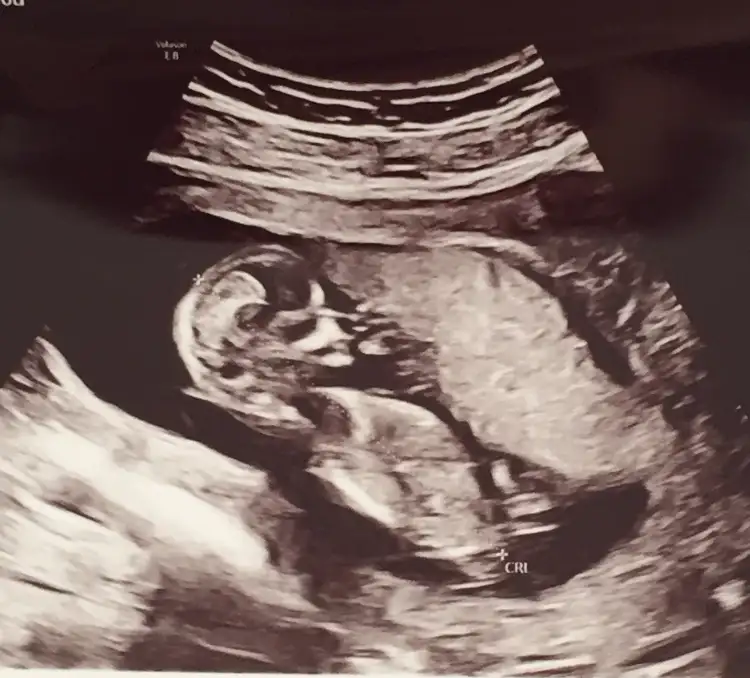

Bu ultrason görüntüsüne bakarmisiniz 🥰11+5di burda Ikra meyra Ikra meyra

benim de 13 haftalık, tahminde bulunur musunuz ?😀

Emin değilim 🙈 sanki erkek gibi başka USG olursa paylaşın